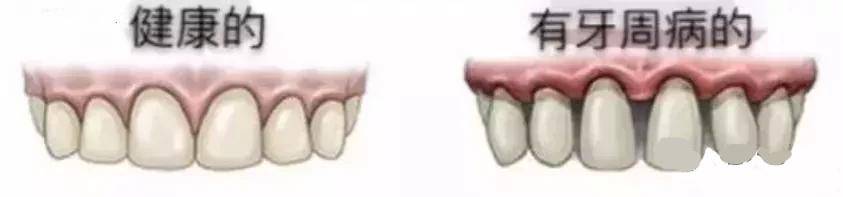

大家都知道,发际线后移会秃头,但你知道吗,牙龈线后移会掉牙!

牙龈线后移,就是牙龈萎缩,简单地说,就是牙龈缘向根尖方向逐渐退缩,像海水退潮一样,暴露出牙根、牙缝,一笑起来,丑得很。

1、牙周炎

牙周炎是造成牙龈萎缩最常见的原因,而且这是一个无法逆转的过程,也就是说,一旦因为牙周炎发生牙龈萎缩,就不可能会好,甚至有时候,牙龈萎缩的“丑状”会在牙周炎治疗后更加明显,更加惨不忍睹。